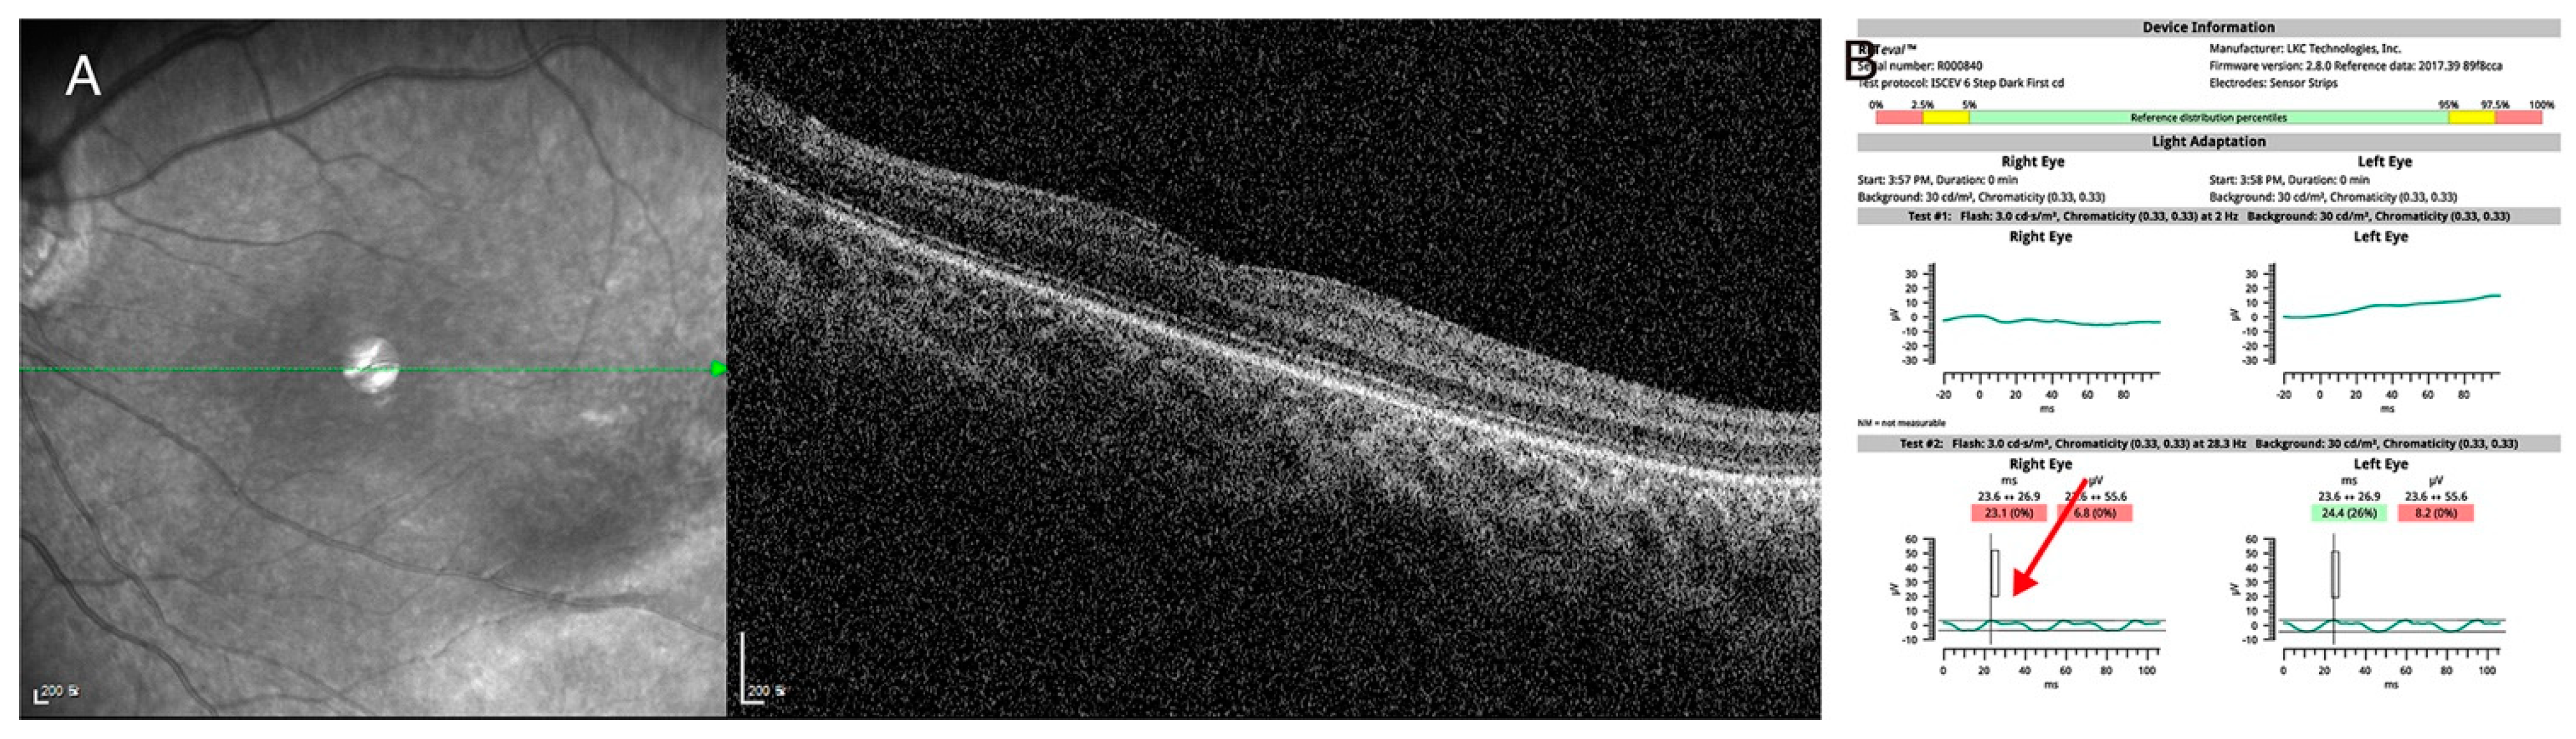

Case study 4 is an example of dual diagnosis in a single patient. A 4-year-old male came to our hospital for the evaluation of upbeat nystagmus. His best-corrected visual acuity was 20/150 in the right eye and 20/100 in the left eye, and mild myopia was noted. Targeted next-generation sequencing showed a novel heterozygous c.1910+1G>A variant in the CACNA1F gene and a novel heterozygousc.3833G>A:p.(Trp1278*) variant in the LRP5 gene. Detailed phenotyping was consistent with the phenotype, and a dual diagnosis was made (Figure 6).

Figure 6.

(P6) A case of dual diagnosis identified by targeted next-generation sequencing (A) Spectralis optical coherence tomography showed mild temporal retinal dragging with shallow fovea pit. (B) Hand-held electroretinogram showed severely attenuated light-adapted 3.0 response and reduced double peak in light-adapted 30 Hz flicker response (red arrow), which was consistent with incomplete congenital stationary night blindness. Targeted next-generation sequencing showed the hemizygous c.1910+1G>A canonical splice site variant in CACNA1F gene and c.3833G>A:p.(Trp1278*) nonsense variant in LRP5 gene. Dual diagnosis of familial exudative vitreoretinopathy and incomplete congenital stationary night blindness was made in this patient, and regular monitoring of bone densitometry was recommended.